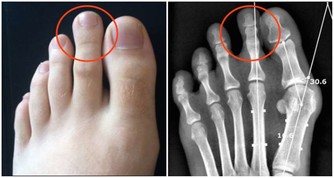

190.【腳骨刺】:沒石子,牙皂各5克,研面,白醋精調煳狀,敷患處固定,2天愈。